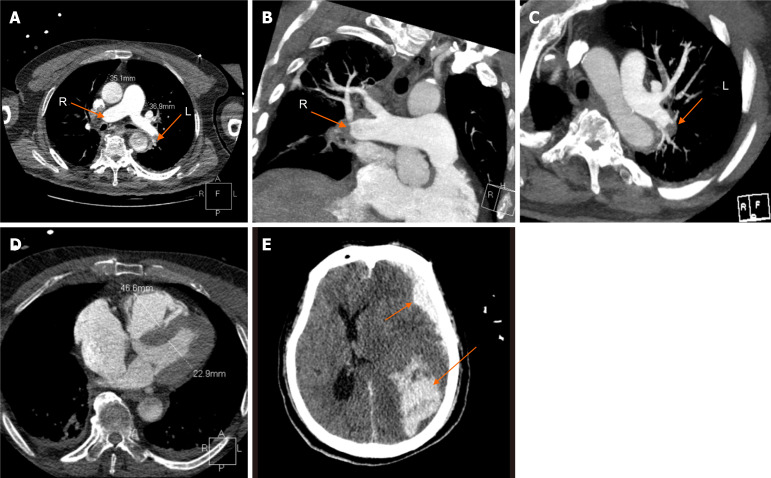

Case summary: We present a case of a 69-year-old male who experienced a prolonged cardiac arrest in an ambulance with pulseless electrical activity. Upon arrival at the emergency department with ongoing manual chest compressions, bedside point-of-care ultrasound revealed an enlarged right ventricle without contractility. Acute PE was suspected as the cause of cardiac arrest, and intravenous thrombolytic therapy with 50 mg tissue plasminogen activator was administered during mechanical chest compressions. Despite 31 minutes of CPR, return of spontaneous circulation was not achieved until 8 minutes after initiation of Veno-arterial extracorporeal membrane oxygenation (ECMO) support. Under ECMO support, the hemodynamic status and myocardial contractility significantly improved. However, the patient ultimately did not survive due to intracerebral hemorrhagic complications, leading to death a few days later in the hospital.